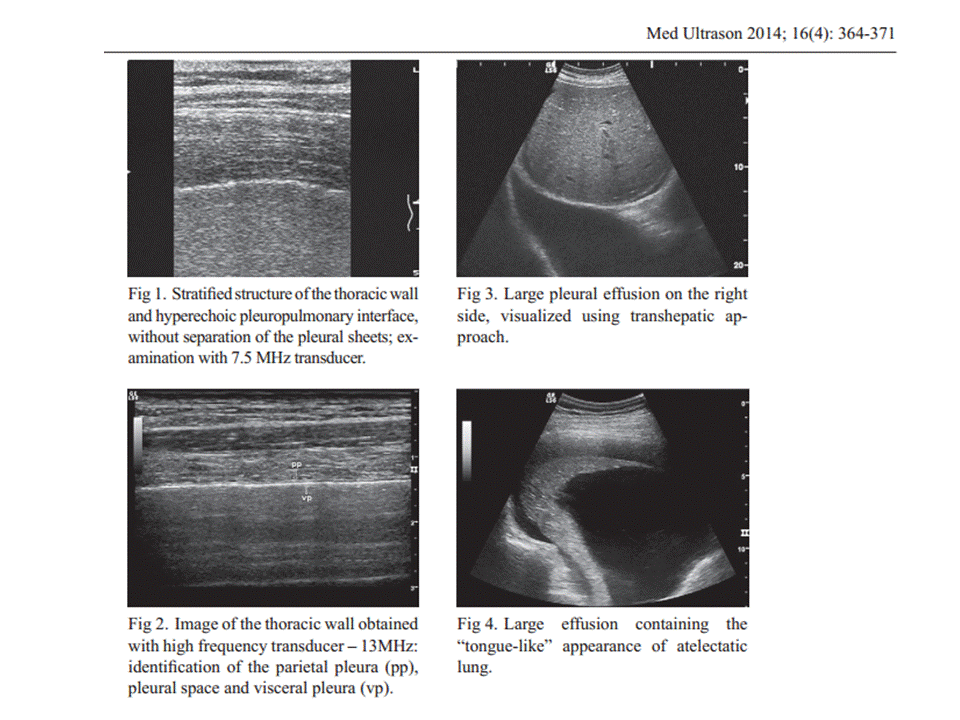

PLEURAL ULTRASOUND

US is a very important diagnostic method for pleural pathology, providing high resolution images, useful in all kinds of clinical scenarios – emergency, diagnostic and interventional ultrasonography. It is superior to chest radiography for the diagnosis of pneumothorax and characterization of pleural effusions. US represents the best method for guiding fluid aspiration and transthoracic biopsy of pleural-based lesions. It is also a reliable method for evaluating the parietal infiltration of the lung tumors, but CT is superior providing more information concerning all parts of the pleura. The limit of this method is the inability to visualize the mediastinal pleura, and the lesions obscured by subcutaneous emphysema and the bony structures of the thorax – scapulae, sternum and the spine. US can provide useful information for almost all pleural pathology and it should be use more extensively for all these reasons, being also accessible, cheap and widely available for many medical specialties.